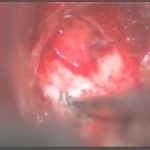

術中写真

摘出 前

摘出 中

摘出 後